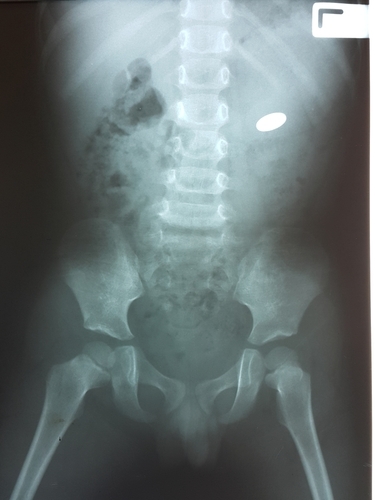

A 50-year-old tribal from Maharashtra's Palghar district has been successfully operated upon on Thursday by doctors to remove 72 coins that the man had swallowed over a long period due to certain mental ilnesses, doctors said.

Dr Amit Kele, who led the team of doctors that operated on Krishna Somalya Sambar, said that Sambar was suffering from a rare case of metallophagia, an impulse to swallow metallic objects.Sambar is a resident of Thoratpada in Talasari taluka of Palghar, he said."He is suffering from 'bezoar'- a gastrointestinal disorder- and 'pica'- a ompulsive disorder of eating non-nutritional substances- for the past 20 years. This made him a habitual eater of iron and metal coins. Some got flushed out of his system in the natural course of excretion but others remained," said Kele today.

The doctor added that this was causing Sambar problems like vomitting and indigestion.Sambar approached the medical team on Thursday and following an X-ray, the doctors proceeded to operate upon him.The doctor added that the endoscopic surgery lasted for three and a half hours and that Sambar's condition was now improving. He would soon be discharged from hospital, Kele added.